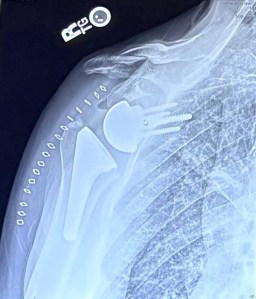

The procedure was a full reverse right (dominant) shoulder replacement. A large portion of the humeral head was removed and replaced with a cup-shaped receptacle mounted on a long titanium stem which was literally pounded into the humerus. On the opposite side of my shoulder a titanium ball mounted on a plate was solidly fastened to the glenoid by four long titanium screws. Essentially, I’ve been screwed, glued and tattooed. The whole shebang happened on May 14th and took just over two hours.

Now I have a $65k titanium right shoulder, which in theory, should outlive the rest of me. So far, it feels pretty damn good. In fact, it feels so good that I’m contemplating doing the same to the left shoulder. I’ve advocated for a balanced physique and currently I’m feeling a little disproportionate. I’m going to give it a little more time just to make sure. My hope is to sneak away with a hard project or two, prior to going through replacement trauma again. I thank science for the discovery of cortisone and modern medicine in the meantime.